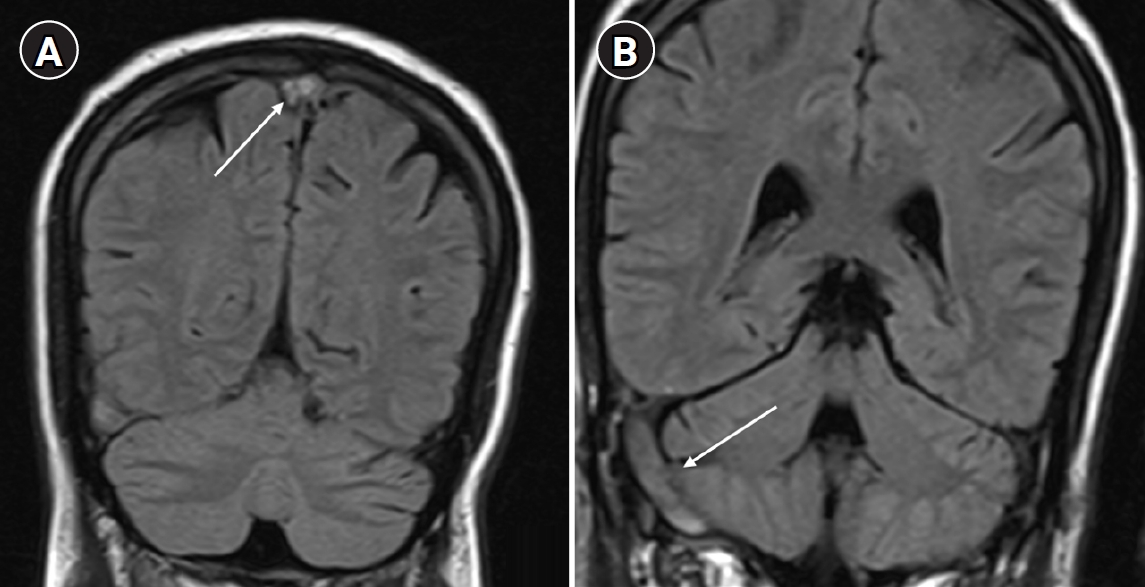

Atherosclerotic changes in an intrasellar persistent trigeminal artery in a patient presenting with dizziness: a case report from Korea

Jieun Byun

, Boeun Lee

Ewha Med J 2026;49(2):e12.